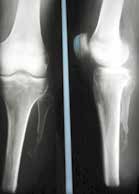

Sehr lange Unterschenkelstümpfe (kurz oberhalb der Spongiosa der distalen Tibia) sind auf die Dauer wegen der Gefahr zunehmender trophischer Störungen über die Jahre auch bei sehr geringem Endkontakt in der Prothese problematisch (Abb. 11). Viele Jahre scheint ein langer US-Stumpf gut versorgbar zu sein, wenn die Amputation im Kindesalter stattfindet und wenn Tibia- und Fibulaende sich fast auf gleicher Höhe befinden und somit eine breitere Auflagefläche für den Endkontakt darstellen (Abb. 12). Gewebe und arterielle Durchblutung stellen sich offenbar im Kindesalter auch besser auf die Gesamtsituation ein. Allgemein gilt aber: Der beste Unterschenkelstumpf ist der, der mit Muskulatur unter physiologischer Vorspannung gedeckt ist.

Der kurze Stumpf (proximales Drittel) bedeutet im Knochen mehr Spongiosa. Das wiederum bedeutet wegen der besseren Lastverteilung eine höhere Stumpfendbelastbarkeit um 80 bis 90 %. Höhere Stumpfendbelastbarkeit bedingt mehr Propriozeption. Somit wird der Verlust besserer Biomechanik gegenüber dem mittellangen Stumpf teilweise ausgeglichen. Die Rehabilitation gestaltet sich in der Regel unkompliziert. Die Entfernung der Fibula ist kein Nachteil für die prothetische Versorgung, da der Stumpf eine Dreiecksform besitzt. Im Gegenteil, das Fibulaköpfchen wird nicht prominent, was die Kurzstumpfversorgung erleichtert.